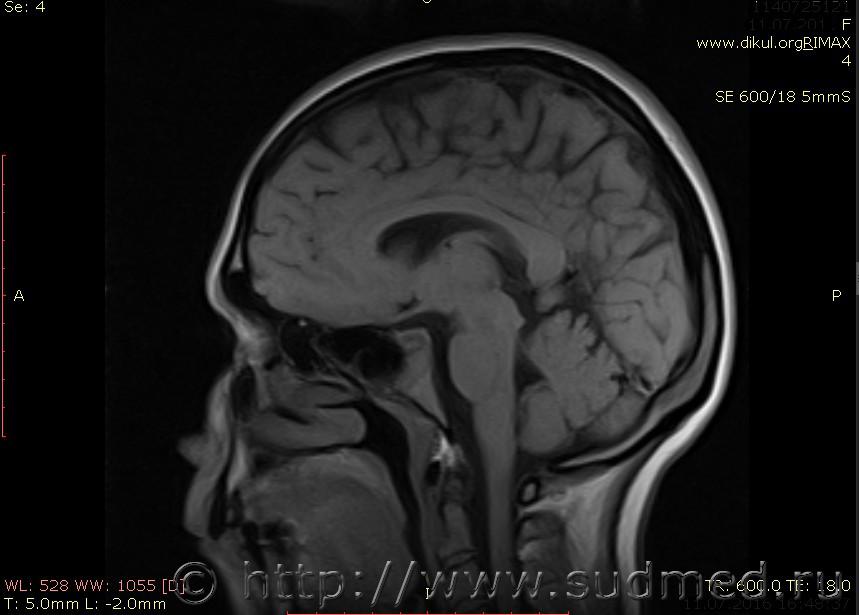

МРТ головного мозга показало: МР-данных за наличие очаговых изменений в веществе головного мозга на момент исследования не выявлено. МР-признаки нарушения соотношения в атланто-осевом суставе. Определяется ассиметрия положения зубовидного отростка С2 относительно боковых масс С1(справа 6,5; слева 4 мм.)

Сама по себе эта информация даёт основания подозревать вывих первого шейного позвонка, но однозначно не свидетельствует о наличии вывиха. Нужно смотреть на снимках наличие реакции со стороны мягких тканей, в т.ч. связочного аппарата, нужно анализировать особенности неврологической патологии, её динамику и проч.

Запрошен электронный вариант снимков из учреждения, где делалось МРТ. Т.к. с самого снимка делать копии не получается,очень мелкие кадры. Завтра попробую вставить в сообщение. (Но СМЭ снимок не смотрел, смотрел только мед.карту, в которой находилось описание МРТ).

Посмотрите пожалуйста снимки, надеюсь на них видны позвонки С1,С2?

Прошу прощения, попробую снова прикрепить файлы. Данные учреждения и пациента убраны.